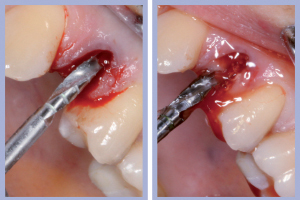

- Figg. 7a, b – Toilette chirurgica

- Figg. 8a, b – Mappatura alveolare tramite sonda parodontale

– Sondaggio alveolare e revisione chirurgica (Figg. 7-8);

Dopo l’estrazione, eseguita con i consueti passaggi di scollamento-lussazione-estrazione, la revisione chirurgica tramite cucchiaio alveolare consentiva la completa rimozione dei frustoli di tessuto di granulazione e di legamento parodontale residuo. La preparazione del sito implantare veniva effettuata con approccio flapless, ovvero senza l’esecuzione del lembo.